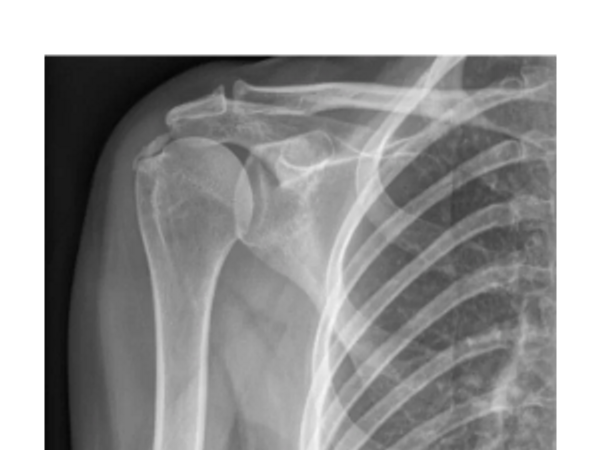

Understand the importance of specific plain films and know the limitations and uses of shoulder imaging.

What to look for on MRI, how to interpret clinically and when US / CT or other specialty imaging is needed.

Diagnostic Imaging